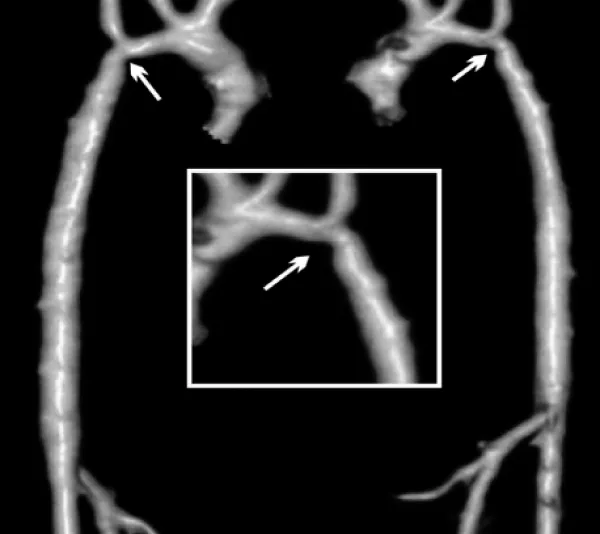

Enalapril was continued and dual anti aggregation was started with clopidogrel and aspirin. On follow-up the femoral pulses were weaker than the right brachial. Blood pressures could not be measured for persistent excessive irritability. At the time of multislice CT under general anesthesia, noninvasive blood pressure showed normal values for the right arm and moderate increase in the coarctation gradient (Table 1). CT imaging findings were no different to those following BA. The descending aorta distal to the stent remained narrowed reassuming a normal caliper at the diaphragm level. Two more BAs for recurrent coarctation were performed at age 3y 5m and 5m later. The former with right axillary artery access for recoarctation distal to the left subclavian artery which had severe ostial stenosis and subclavian steal (Figure 4A). The intrastent intimal proliferation was much less prominent than in the previous procedure and the coarctation diameter almost doubled (Figure 4B). The other intervention from the right femoral artery addressed the sub-clavian stenosis with disappearance of subclavian steal. The patient continues with antihypertensive and dual antiaggregation therapy. An extended patch angioplasty is expected in the future (Figure 4 A,B).

Figure 1: Multi-slice CT at the age of 5 months. There is recurrent coarctation of the aorta (arrow) with hypoplasia of the transverse arch extending to the thoracic aorta (see text for diameters at different levels).